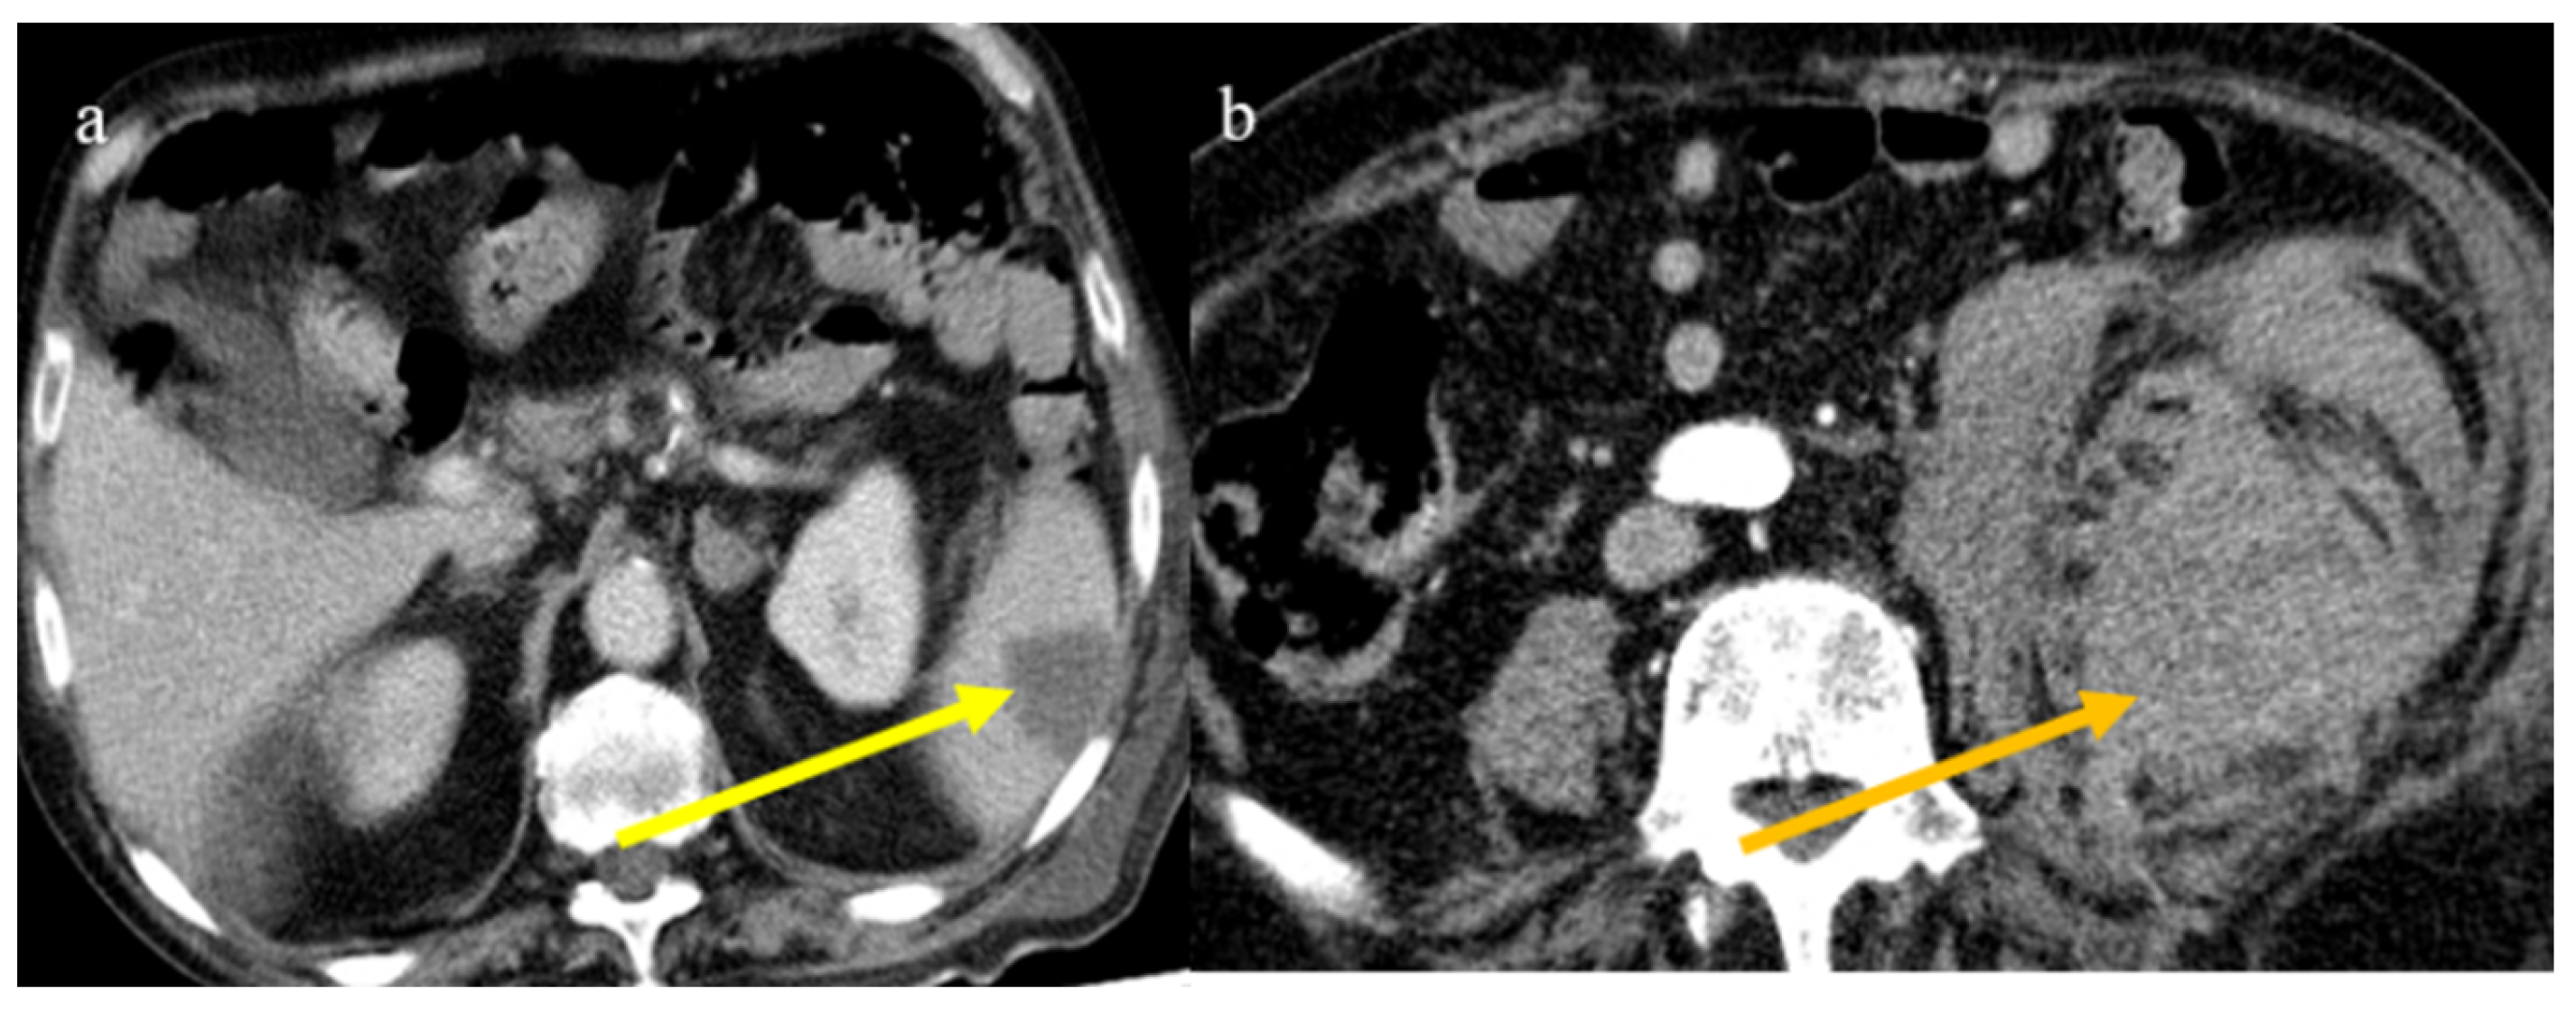

- Bonaffini, P.A.; Franco, P.N.; Bonanomi, A.; Giaccherini, C.; Valle, C.; Marra, P.; Norsa, L.; Marchetti, M.; Falanga, A.; Sironi, S. Ischemic and hemorrhagic abdominal complications in COVID-19 patients: Experience from the first Italian wave. Eur. J. Med. Res. 2022, 27, 1–9. [Google Scholar] [CrossRef]

- Peshevska-Sekulovska, M.; Boeva, I.; Sekulovski, M.; Zashev, M.; Peruhova, M. Gastrointestinal Ischemia—Stumbling Stone in COVID-19 Patients. Gastroenterol. Insights 2022, 13, 206–217. [Google Scholar] [CrossRef]

- Norsa, L.; Bonaffini, P.A.; Caldato, M.; Bonifacio, C.; Sonzogni, A.; Indriolo, A.; Valle, C.; Furfaro, F.; Bonanomi, A.; Franco, P.N.; et al. Intestinal ischemic manifestations of SARS-CoV-2: Results from the ABDOCOVID multicentre study. World J. Gastroenterol. 2021, 27, 5448–5459. [Google Scholar] [CrossRef]

- Ojha, V.; Mani, A.; Mukherjee, A.; Kumar, S.; Jagia, P. Mesenteric ischemia in patients with COVID-19: An updated systematic review of abdominal CT findings in 75 patients. Abdom. Imaging 2021, 47, 1565–1602. [Google Scholar] [CrossRef]

- Boraschi, P.; Giugliano, L.; Mercogliano, G.; Donati, F.; Romano, S.; Neri, E. Abdominal and gastrointestinal manifestations in COVID-19 patients: Is imaging useful? World J. Gastroenterol. 2021, 27, 4143–4159. [Google Scholar] [CrossRef]

- Keshavarz, P.; Rafiee, F.; Kavandi, H.; Goudarzi, S.; Heidari, F.; Gholamrezanezhad, A. Ischemic gastrointestinal complications of COVID-19: A systematic review on imaging presentation. Clin. Imaging 2020, 73, 86–95. [Google Scholar] [CrossRef] [PubMed]